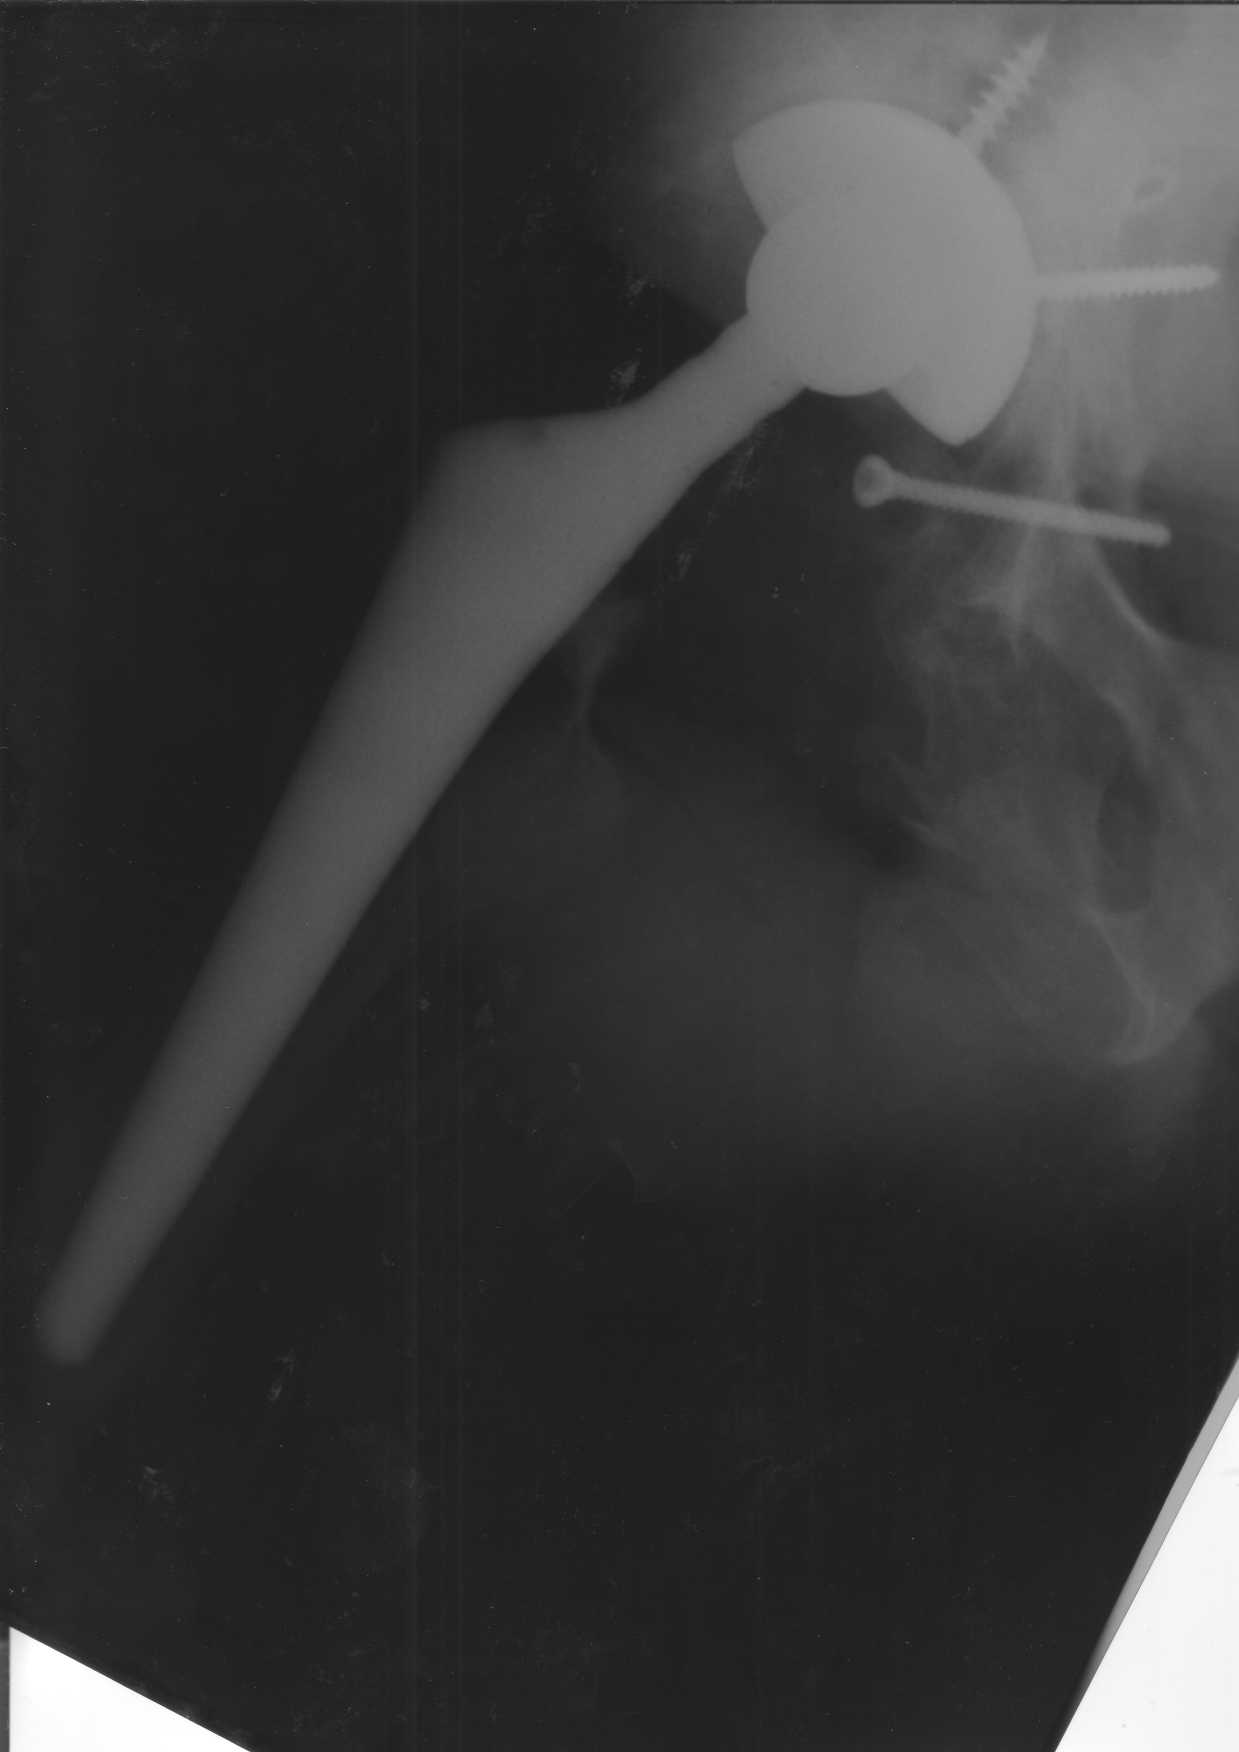

Уважаемые коллеги.В 3 Центральный Военный Клинический Госпиталь имени А. А. Вишневского, что в Красногорске, Московской области, в отделение эндопротезирования крупных суставов поступил пациент 1960 года рождения Жалобы при поступлении: на боли в области левого тазобедренного сустава (больной указывает на точку расположенная в середине условной линии между седалищным бугром и большим вертелом), усиливающиеся в начале ходьбы, при опоре на левую ногу с иррадиацией болей по наружной и наружно-задней поверхности левого бедра, левый коленный сустав; снижение объема движения в левом тазобедренном суставе, снижение опорной способности левой нижней конечности, хромоту на левую ногу, необходимость использования дополнительной опоры (костыли) при ходьбе, снижение объема двигательной активности из за болей в суставе.В анамнезе: Со слов больного, согласно медицинских документов, в 1989 году получил травму левой нижней конечности: закрытый перелом левой вертлужной впадины с центральным вывихом головки левой бедренной кости. Лечился консервативное. В процессе лечения сформировался посттравматический артроз, укорочение левой нижней конечности до 5 см. 25.04.2005 года в Подольском Окружном Госпитале Министерства Обороны выполнено: одномоменто, остеосинтез заднего края вертлужной впадины фрагментом резецированной головки бедренной кости и тотальное эндопротезирование левого тазобедренного сустава бесцементным эндопротезом "VERSIS ET" с бесцементной чашкой TRILOGY. Послеоперационный период осложнился ранним нагноением области эндопротеза, в результате санаций очага инфекции и антибиотикотерапии, активного промывного дренирования антисептиками, послеоперационная рана зажила. После операции, со слов больного, через два месяца в полном объеме стал нагружать левую нижнюю конечность. В течение полгода, после операции чувствовал себя вполне удовлетворительно. С марта 2006года стал отмечать появление болей в области тазобедренного сустава, то в области паха, то в области левой ягодицы. С августа месяца отмечает те жалобы, с которыми он сейчас к нам обратился. Температура тела, после заживления раны, нормальная. В анализах крови, лейкоциты около 7 тыс, формула нормальная, СОЭ 12 мм ч. Локально: при осмотре обеих нижних конечностей, анатомическая ось конечности не нарушена; отмечено относительное укорочение левой н\конечности на 1.5 см., гипотрофия мышц левого бедра 3 см, голени 2 см, симптом. Объем движений в тазобедренных суставах: правый~ сгибание- 60 гр, разгибание-180 гр ,отведение- 35 гр, левый~ сгибание- 110 гр , разгибание-170 гр , отведение-15 гр. Контуры других суставов н/конечностей обычные, объем движений в них не страдает. Пульсация на артериях конечностей удовлетворительная. Неврологические нарушения конечностей отсутствуют, рефлексы на обеих н/конечностях одинаковые, чувствительных нарушений нет. Осевая нагрузка на левую нижнюю конечность вызывает боль в точке расположенная в середине условной линии между седалищным бугром и большим вертелом. Отмечается пигментация и пастозность нижней трети обеих голеней и стоп, характерная для посттромботической болезни. На Цветном дуплексном сканировании сосудов нижних конечностей: Нестенозирующий атеросклероз обеих бедренных и подколенных артерий . Гемодинамически значимых препятствий кровотоку в магистральных артериях ног не выявлено. Глубокие и поверхностные вены нижних конечностей проходимы. Умеренная недостаточность клапанов подколенных вен. Данных за тромбоз глубоких вен на момент осмотра не получено.А вот что пишет наш рентгенолог: На серии рентгенограмм области левого тазобедренного сустава определяется тотальный бесцементный эндопротез. Вокруг тени чашки эндопротеза определяется ободок остеорезорбции. Кроме того, визуализируется деформированный костный винт фиксирующий консолидированный отломок вертлужной впадины, вплотную прилегающий к тени чашки эндопротеза. Заключение: Рентгеновские признаки нестабильности чашки тотального эндопротеза. Лучевая нагрузка: 6 мЗв. У нас в отделении разошлись мнения: начальник мой утверждает, после сравнения снимков, принесенных больным от августа и октября 2006года и наших рентгенснимков, что у больного нет нестабильности вертлужного компонента, и что надо назначит курс консервативной терапии: препараты кальция, миакальцик, увеличить осевую нагрузку на левую нижнюю конечность, ЛФК направления на укрепление мышц бедра, ягодиц, физиолечение. А я утверждаю, что у больного клиника нестабильности вертлужного компонента, и необходима ревизия вертлужного компонента, не исключено даже наличие инфекции под чашкой эндопротеза (не смотря на отсутствие клинических признаков инфекции). В результате проводимой консервативной терапии, боли у больного усилились. Помогите рассудить нас, мы готовы выслушать ваши мнения по этому поводу. С уважением Батал Шушания.3 ЦВКГ имени А. А. Вишневского